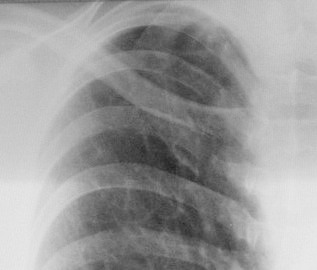

Осумкованный плеврит? в заднем отделе левого синуса.Так ли это?

Собираюсь на консультацию к кардиологу и сегодня сделала рентген в 2 проекциях. И Врач-ренгинолог меня просто ошарашил дословно: Осумкованный плеврит? в заднем отделе левого синуса.

Однозначно, что именно "осумкованного плеврита", в данном случае нет. Однако архивчик есть, да и верхушечки внимания требуют.

Вероятно левосторонняя пневмония в 3-м сегменте.

Здрасти . У вас по снимкам легочный рисунок резко усилен с обоих сторон , справа корень расширен и деформирован .Слева в синусе похоже небольшое количество жидкости ,но насчет осумкованности я сильно сомневаюсь . Вы анализы сдавали ? СОЭ, лейкоциты ..... Верхушки чистые , но вот справа корень и легочный рисунок мне не нравтся , да и что может вызвать выпот в плевральную полость . Было бы хорошо если бы вы сделали манту

Пока анализы не сдавала. Назначена сдача на понедельник. А с права не может быть это после операции на сердце т.к. ее делали именно справа.